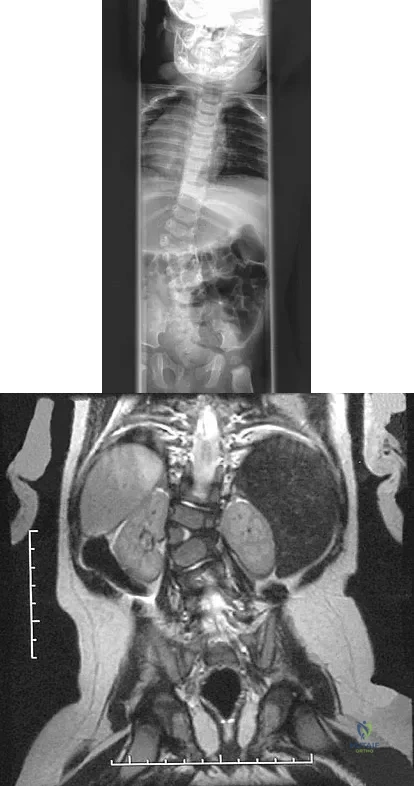

Figures 25a and 25b show the radiograph and MRI scan of a 7 1/2-year-old boy who has been limping for 1 year. His pain has worsened over the past 2 weeks, and his parents note swelling over the dorsum of the foot for the past 4 days. Examination reveals no fever, and laboratory studies show a WBC of 6,700/mm3, an erythrocyte sedimentation rate of 26 mm/h, and a normal C-reactive protein level. What is the most likely diagnosis?

Figures 31a and 31b show the radiograph and MRI scan of an otherwise normal 3-month-old infant who has a spinal deformity. MRI reveals no intraspinal anomalies. What is the next step in management?